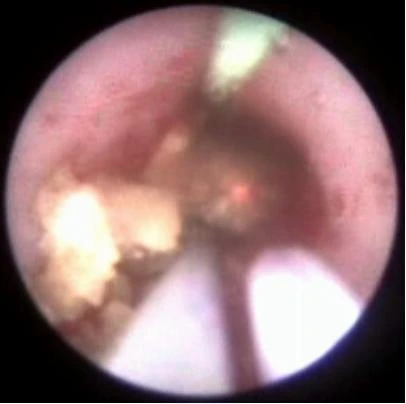

Добившись нужной дисперсности фрагментов камня, их элиминируют корзинкой, либо другими видами экстракторов (петли, щипцы). Производится эндоскопическая ревизия мочеточника. Подтверждается полное удаление фрагментов камня. Уретеропиелоскоп удаляется.